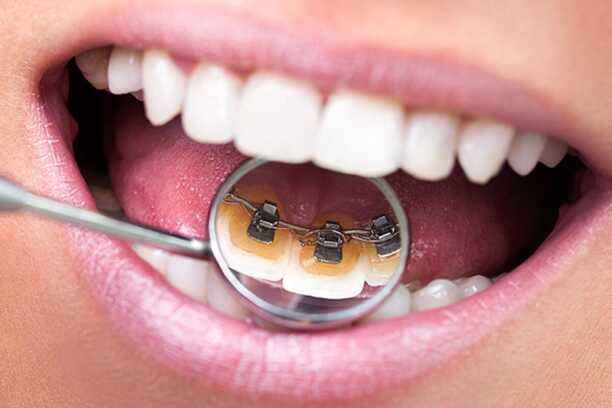

3- تقويم الأسنان اللغوي

خيار متقدم لمن يبحث عن أقصى درجات الخصوصية:

- يُثبت على السطح الداخلي للأسنان.

- غير مرئي تمامًا من الخارج.

- يتطلب خبرة عالية في التركيب والمتابعة.

- مناسب للمهنيين والشخصيات العامة.

- يقدم نتائج فعالة دون التأثير على المظهر الخارجي.